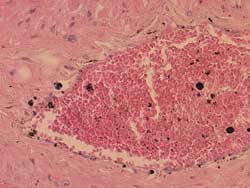

血管内のホルマリン色素

)ホルマリン固定した組織標本で認められる黒褐色調の粒子をいう.血管内や出血など赤血球の存在する場所に認められる.この色素は固定液が pH3.0〜5.0でになると著しく沈着してくる.